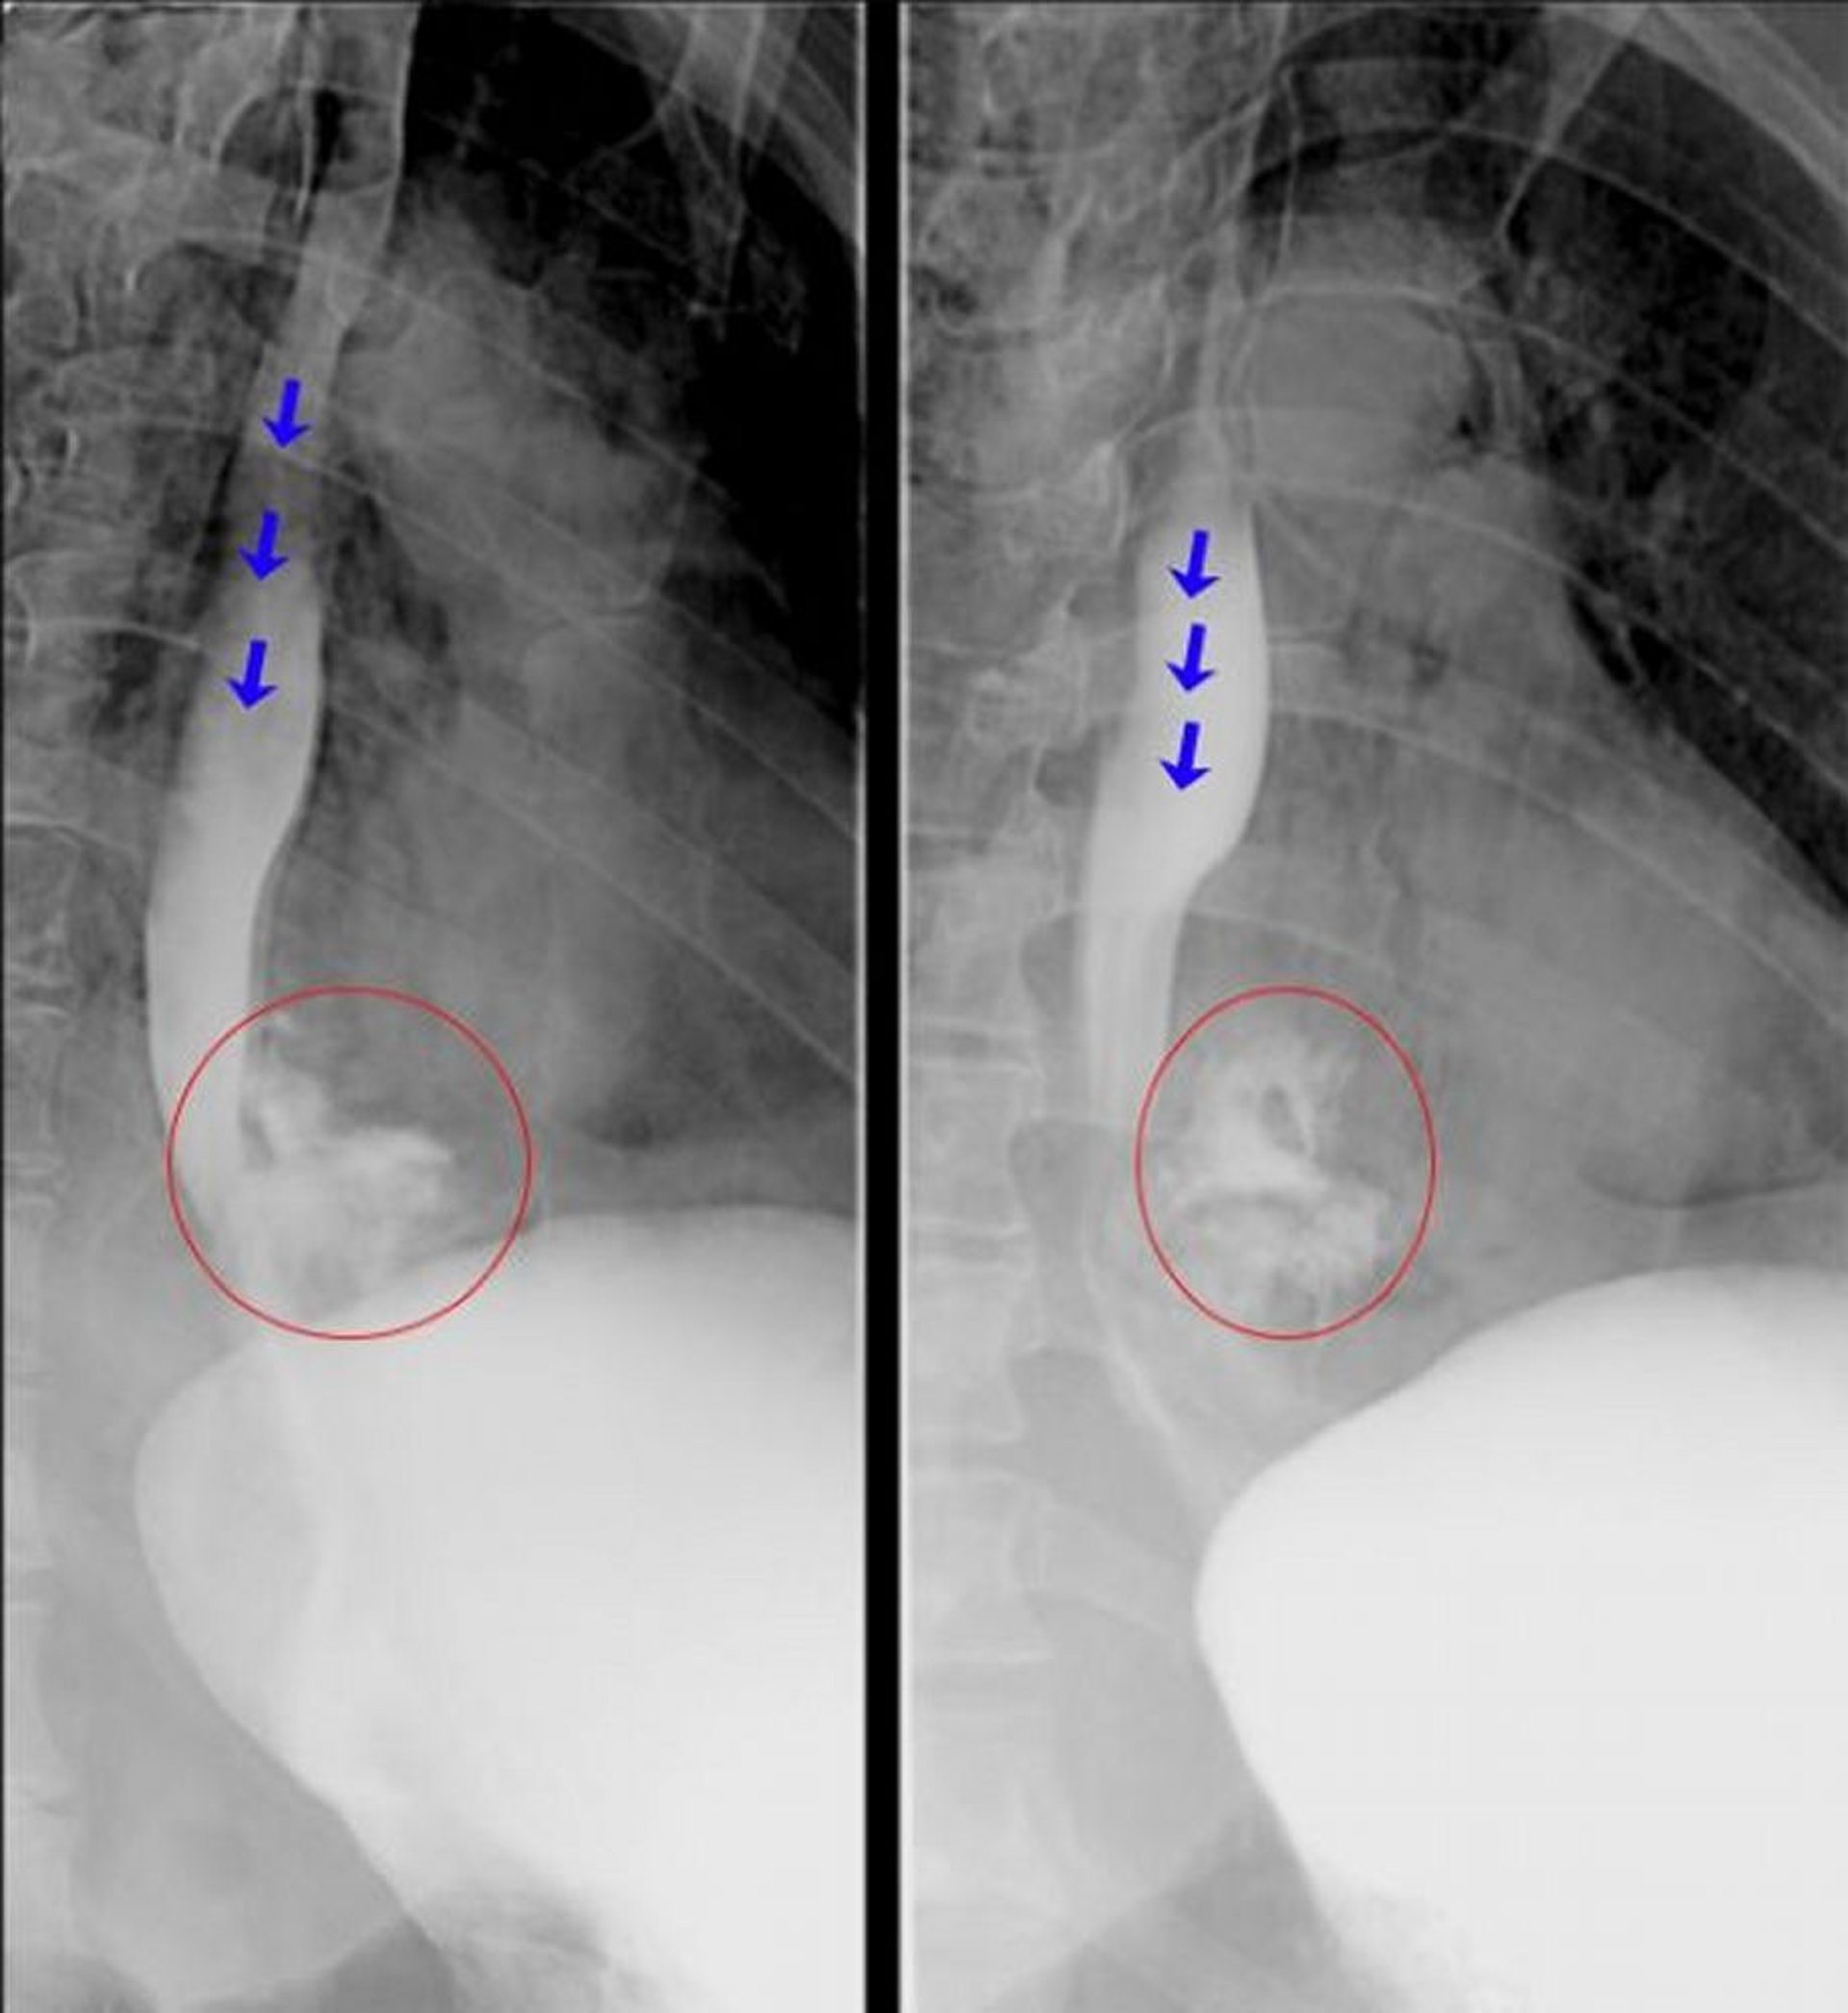

Esofagografia com contraste hidrossolúvel

Esses esofagogramas fluoroscópicos mostram extravasamento franco do material de contraste pelo esôfago distal, consistente com perfuração esofágica. As setas azuis destacam o material de contraste no interior do lúmen do esôfago. Os círculos vermelhos destacam o material de contraste que extravasou para fora do esôfago.